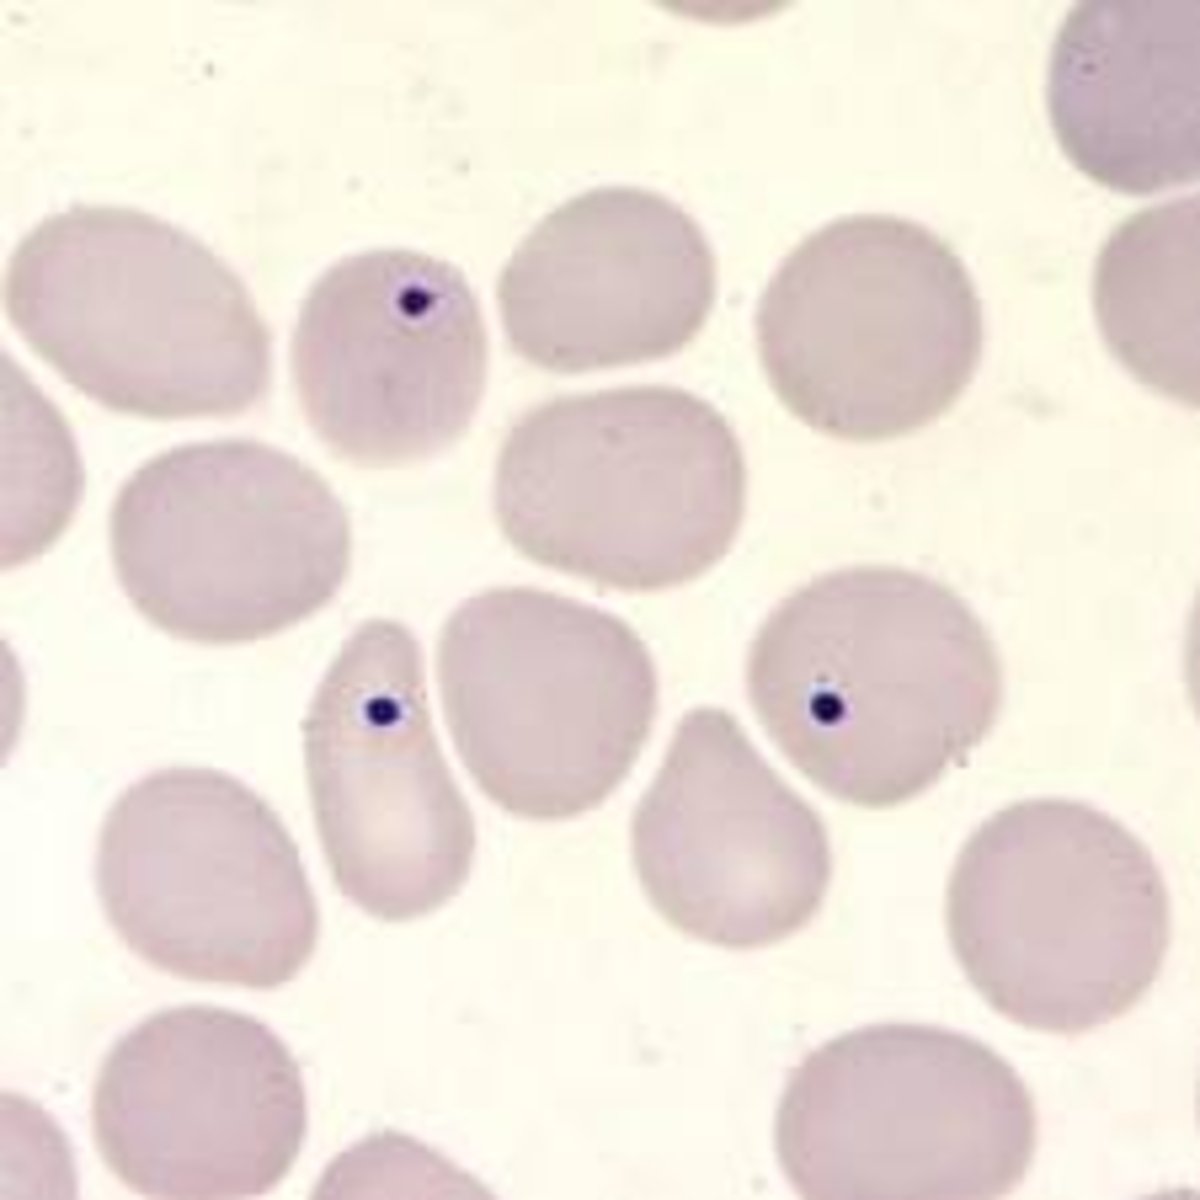

haemorgregarine

exotic hemoparasite

larger than the hosts nucleus

RBC